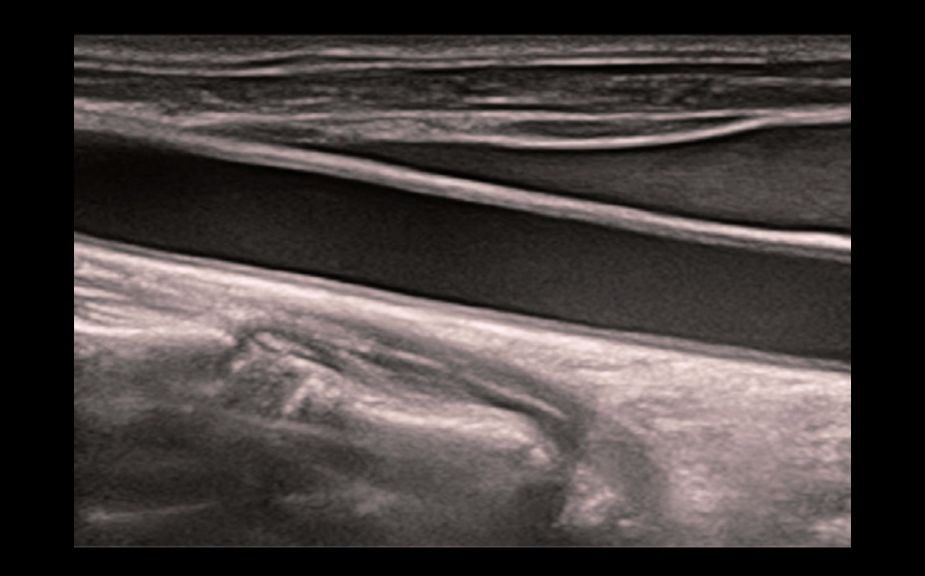

Инновационная оценка жесткости: HiFR STE

В 10 раз более высокая частота кадров при работе режима STE

Высокая чувствительность к движению для повышения стабильности и точности

HiFR STE новообразования молочной железы

Инновационная оценка жесткости: HiFR STE

В 10 раз более высокая частота кадров при работе режима STE

Высокая чувствительность к движению для повышения стабильности и точности

HiFR STE новообразования молочной железы